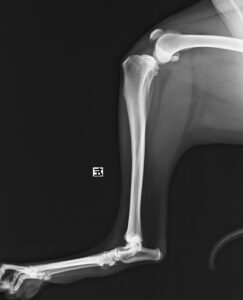

ジャンプした拍子に右後肢跛行とのことでかかりつけ医を受診後、セカンドオピニオンとして当院の整形外科に来院されました。若い雄猫に多く見られる「大腿骨頭すべり症」と診断。ご家族様と相談の上、骨頭切除を実施しました。経過は順調でしたが、その6ヶ月後に逆側も同様に骨折し、同治療を行いました。結果的に両側の骨頭切除が行われましたが、経過は良好です。